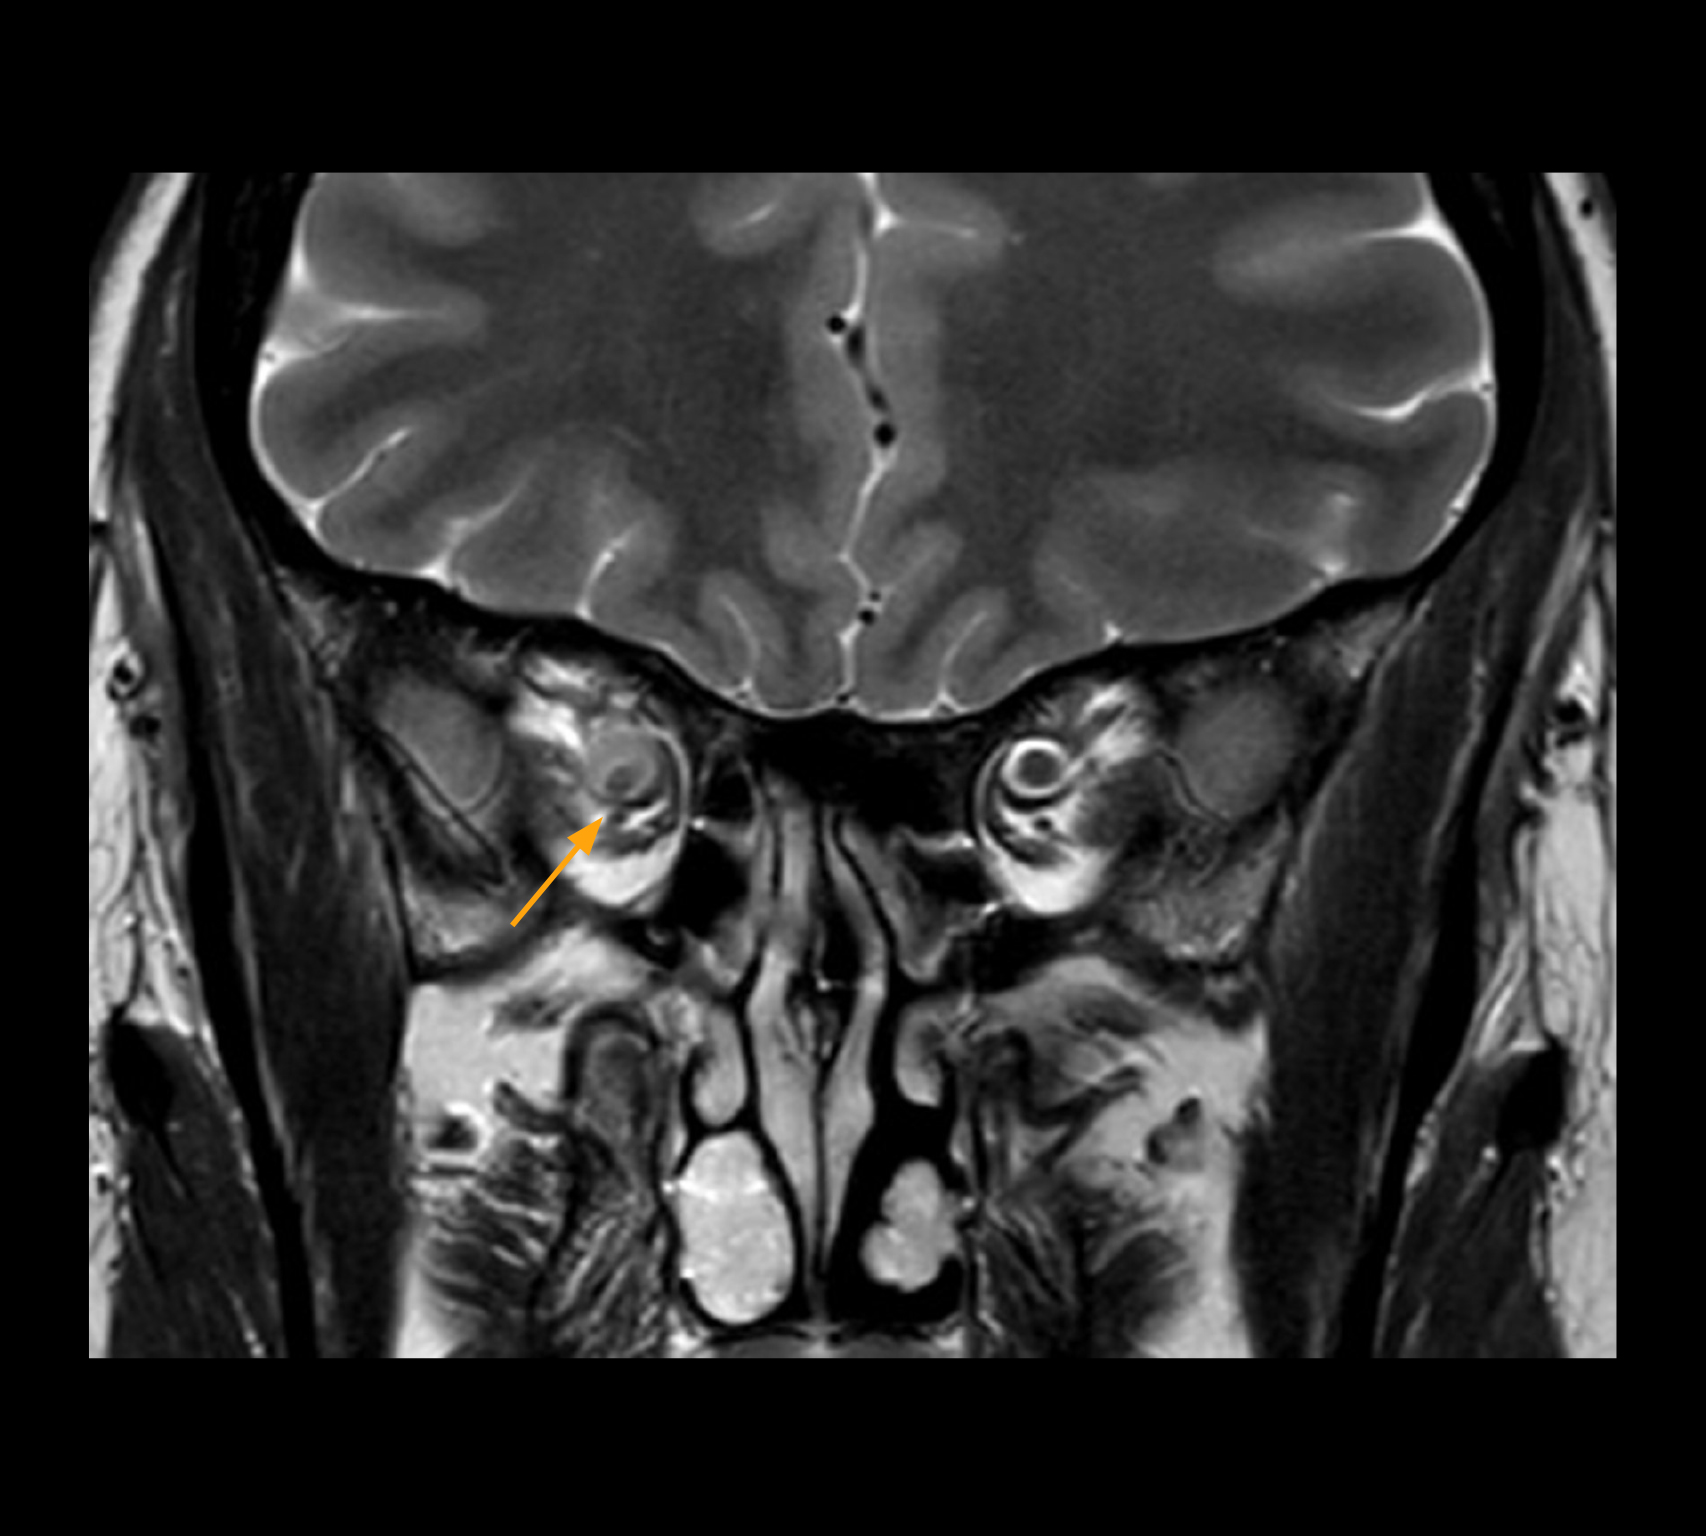

Imaging of the optic nerve sheath

High-resolution MRI impressively demonstrates the compression and narrowing of the right optic nerve in this case of optic nerve sheath meningioma (ONSM). The coronal T2-weighted images show the hyper-intense, half-moon shaped lesion, that is clearly visible in the axial T1W image after contrast injection (right). These imaging findings were so convincing that there sponsible neurosurgeon did not consider a pretherapeutic histological clarification.

High resolution-MRI impressively demonstrates the compression and narrowing of the right optic nerve in this case of optic nerve sheath meningioma (ONSM). The coronal T2-weighted images show the hyper-intense, half-moon shaped lesion, that is clearly visible in the axial T1W image after contrast injection (right). These imaging findings were so convincing that there sponsible neurosurgeon did not consider a pretherapeutic histological clarification.